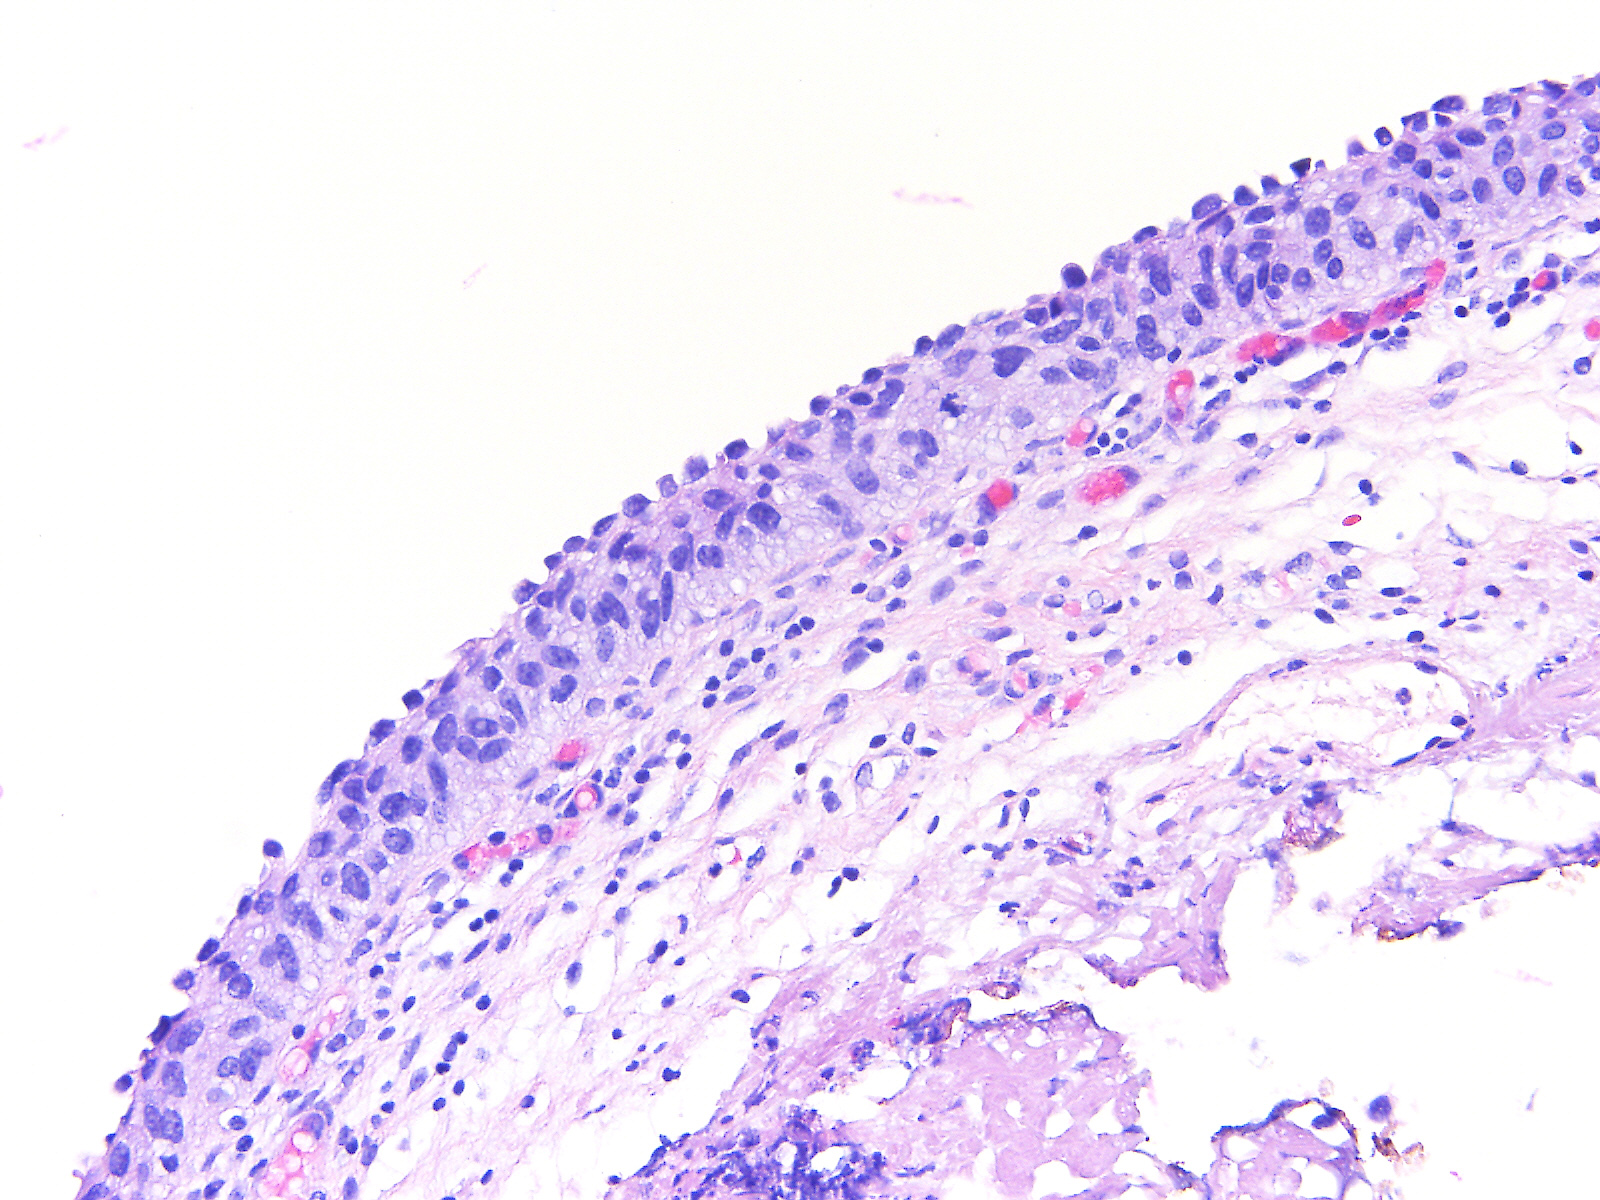

Consensus grade: Carcinoma in situ (CIS)

A 60-year-old female underwent a bladder cystoscopy and biopsy of a 2-cm erythematous lesion at the right posterior bladder wall. About 5 years ago, she was diagnosed with pT1 bladder urothelial carcinoma treated with intravesical therapy.